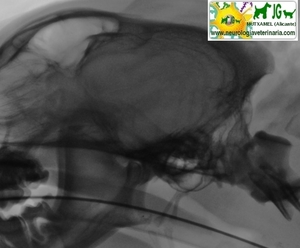

Radiografía digitalizada de cachorro de Siberian Husky con severo trauma craneal |